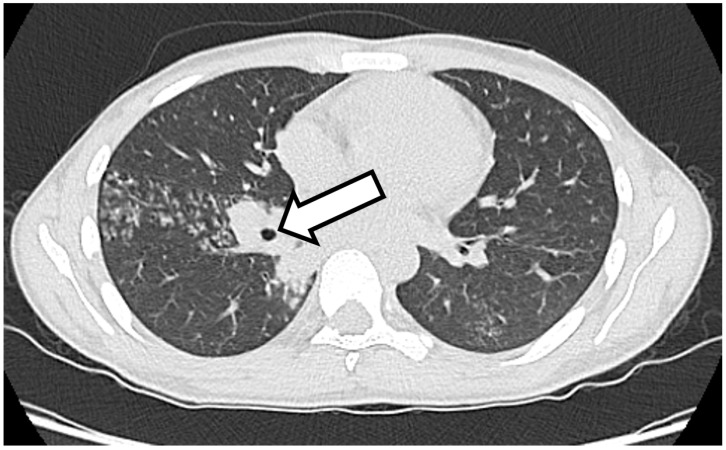

Background: The appearance of new clinical manifestations (for example, subcutaneous or skin abscesses) during anti-tuberculosis treatment is generally indicative of therapeutic failure. The cause of therapeutic failure may be the presence of a drug-resistant Mycobacterium infection or to the failure to achieve a sufficient concentration of the drugs in the bloodstream. Case report: Here, we report the case of a 25-year-old man suffering from tuberculosis infection with lymph-node and pulmonary involvement and an atypical response to specific therapy. Two weeks after starting four-drug antitubercular treatment, the patient began to experience fever, pain and functional impotence in the left foot and ankle, with subsequent evidence of ankle and tarsal osteomyelitis. Four weeks after starting treatment, the patient presented with several widespread, painful subcutaneous abscesses on the trunk, back and right lower limb. Drainage was performed from the ankle and from one of the abscesses, and polymerase chain reaction (PCR) showed a positive result for M. tuberculosis in both samples, with the absence of resistance to drugs. Anti-tubercular medications were continued, with resolution of the pulmonary and bone involvement but with persistence of subcutaneous abscesses, although subsequent drainages showed the absence of mycobacterium tuberculosis. Conclusions: We describe an unusual presentation of paradoxical reaction in the form of osteomyelitis and subcutaneous abscesses in an immunocompetent TB patient, and we reported other similar cases of paradoxical reactions described in the literature in the last ten years, which demonstrate the importance of considering paradoxical reactions in patients who present with new or worsening signs and symptoms after starting tuberculosis treatment.